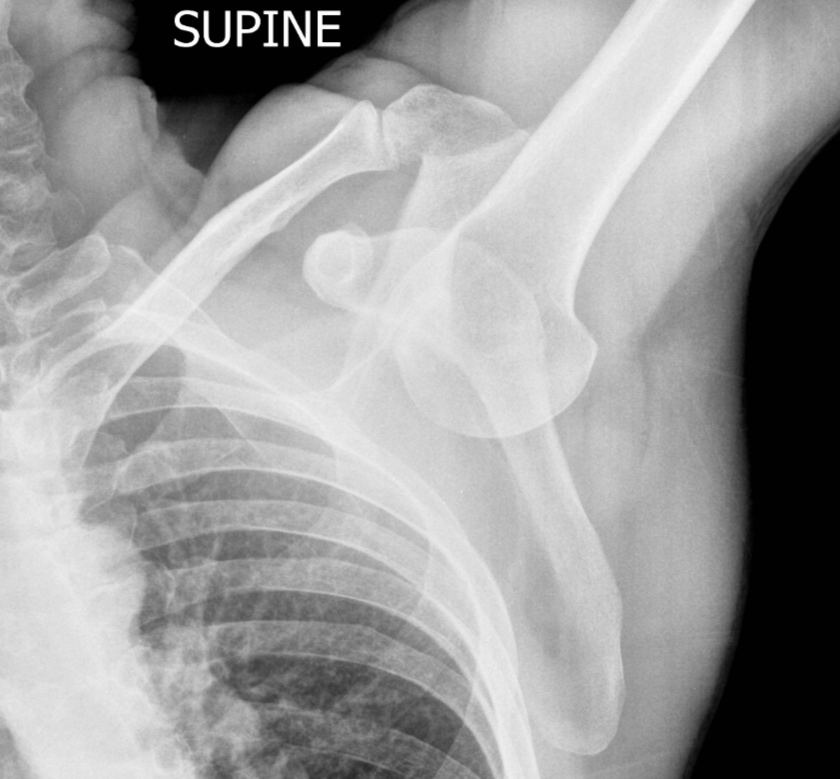

Inferior glenohumeral dislocation